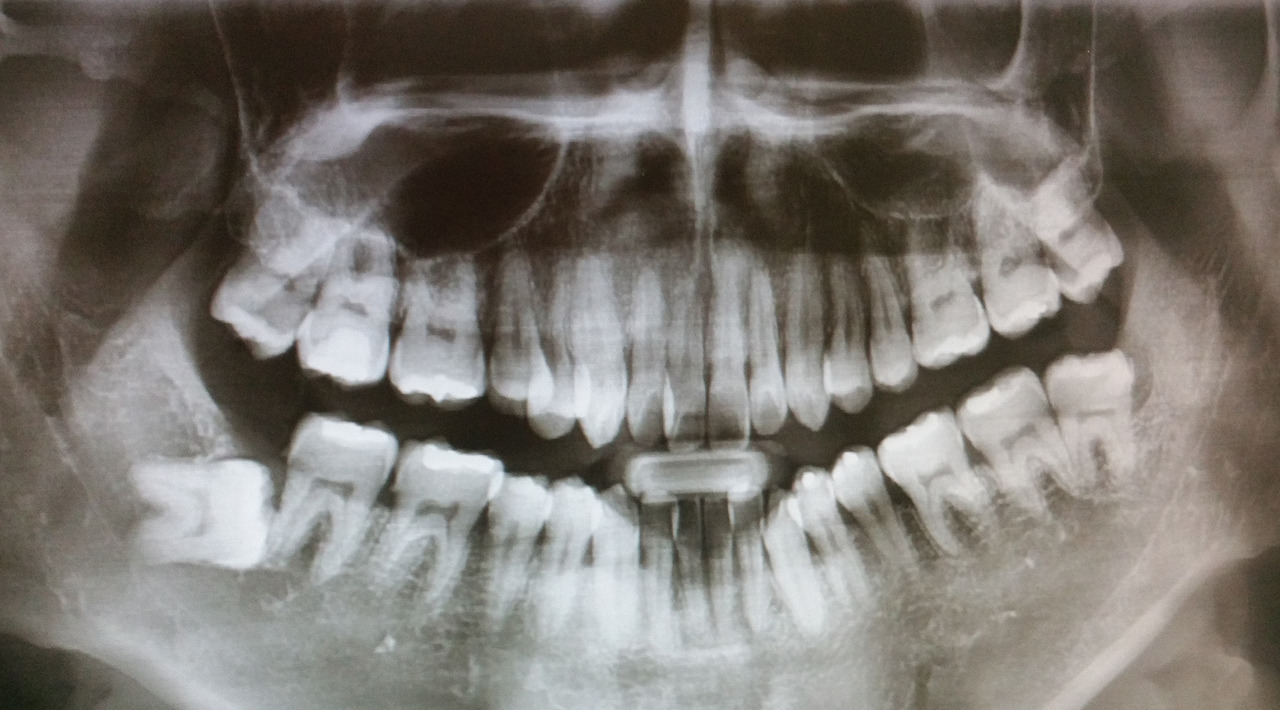

치과를 방문할수록 신뢰는 깊어졌고 드디어 사랑니를 뽑는 날이다. 총 4개의 사랑니 중 우측 아래는 완전히 옆으로 누워있었는데, 잇몸 속에 있고 특별한 증상이 없으니 그냥 두자고 했다. 다행이다. 엑스레이만 봐도 이건 보통 일이 아니라는 것을 알 수 있다. 좌측 위아래를 뽑고 일주일 후 우측 위를 뽑기로 했다.